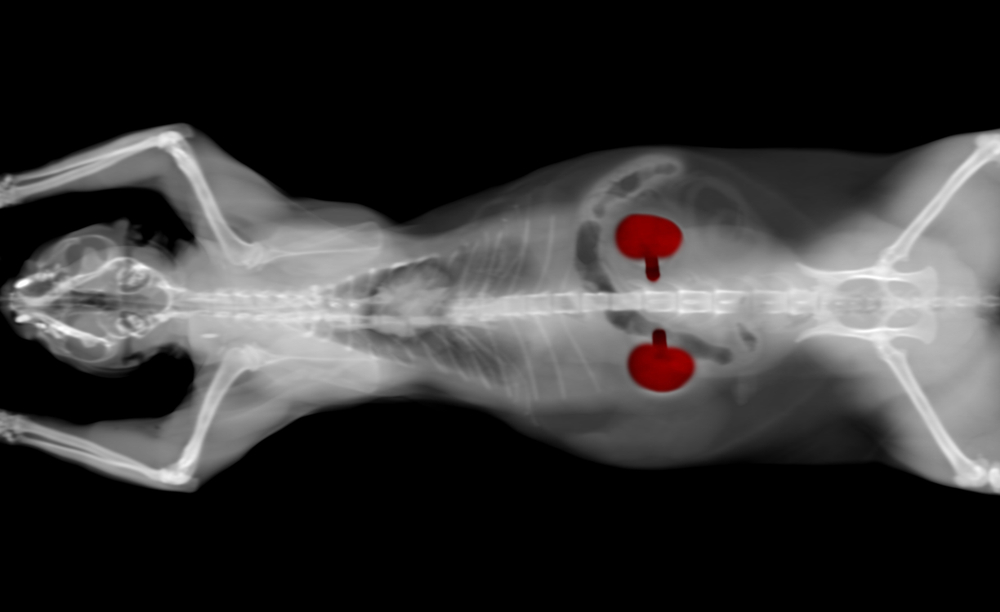

Chronic kidney disease (CKD) often goes undiagnosed and untreated because pets don’t exhibit signs until their condition is advanced. Symmetric dimethylarginine (SDMA) is an important CKD screening test, and our Family Veterinary Care of Oakdale team explains five reasons why this diagnostic tool is so important when evaluating your pet’s health status.

#1: Chronic kidney disease causes significant health problems for your pet

Kidney health is critical to proper body functioning. If your pet has CKD, their damaged kidneys cannot adequately perform these vital processes:

- Removing toxins from the body — Tiny filters (i.e., nephrons) make up the kidneys, which are responsible for removing toxins from the body. CKD interferes with this function, allowing waste material to accumulate in the bloodstream.

- Regulating red blood cell (RBC) production — The kidneys make the hormone erythropoietin, which is responsible for signaling the bone marrow to produce RBCs. Without this hormone, nonregenerative anemia occurs.